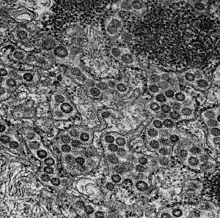

MRC-5 (Medical Research Council cell strain 5) is a diploid cell culture line composed of fibroblasts, originally developed from the lung tissue of a 14-week-old aborted white male fetus.[1][2] The cell line was isolated by J.P. Jacobs and colleagues in September 1966 from the seventh population doubling of the original strain, and MRC-5 cells themselves are known to reach senescence in around 45 population doublings.[2][3][4]